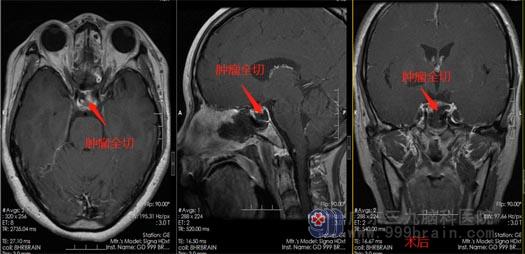

受限于当地医疗条件,黄女士在丈夫的陪同下来到了广东三九脑科医院神经外五科,排除手术禁忌症后,外五科手术团队在全麻下为黄女士实施了“内镜经鼻鞍区占位切除术+颅底重建术”,手术顺利,术中肿瘤全切,垂体保护良好,出血仅100ml。

术后黄女士生命体征平稳,鼻腔没有渗血渗液,没有尿崩,离子情况稳定,泌乳素由之前的2055ng/ml降为291ng/ml。经鼻孔行微创手术就可以切除脑袋里的肿瘤,这让黄女士一家感到非常神奇。